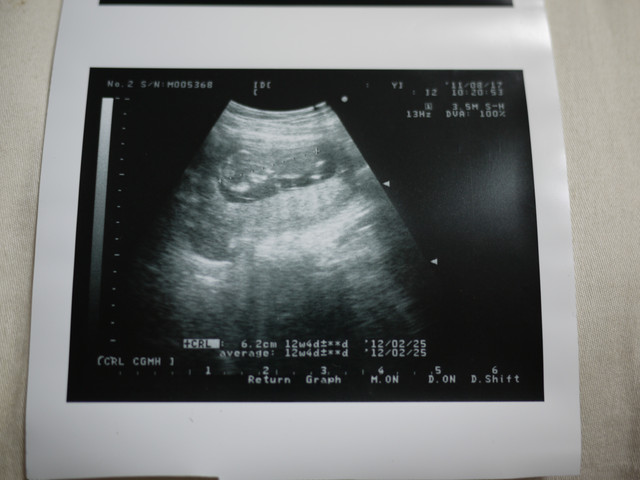

這次給小卡po了張超音波照

因為這張就是他的男性特徵了

小卡是個男寶寶

重點來了,寶寶的性別

醫生說看起來像男生

不過性別特徵還不是很明顯

但男生的機率很大

下個月再確定

己經確定是男生了